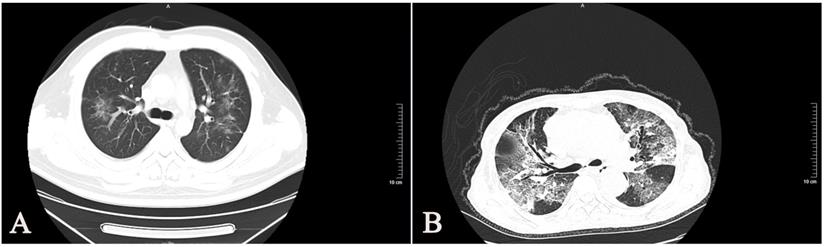

All of the 30 enrolled patients showed bilateral involvement of the chest CT scan (Table 1). Most patients with SARS-CoV-2 had typical imaging features, such as GGOs (ground-glass opacities), mixed GGOs, and consolidation (Fig 4). We found that the CT manifestations of severe and critically ill patients were more serious than those of moderate patients.

Figure 4

Chest CT images of SARS-CoV-2 infected patients. (A) A38-year-old man with confirmed SARS-CoV-2, moderate type. CT images show bilateral diffuse ground-glass opacities. (B) A 66-year-old woman with confirmed SARS-CoV-2, critically ill type. CT images show bilateral diffuse ground-glass opacities and reticulation.